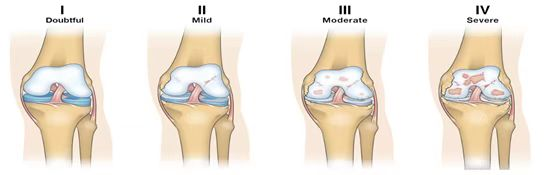

手术治疗: 目前,公认的保膝治疗有关节镜手术、单髁置换手术、胫骨高位截骨手术,由于保留前后交叉韧带,拥有较好本体感觉,术后并获得较高的运动能力和关节屈伸活动能力。后者胫骨高位截骨术,由于钢板设计改进,开放楔形胫骨高位截骨术具有更多的优点,给病人带到更多的好处。术后可以减轻疼痛,改善功能,极大的提高了生活质量,并且在一些情况下延迟疾病进展的治疗。 膝关节骨性关节炎分为4期,骨关节炎病情越长,软骨损害越重,症状也就越重。但临床观察,由于患者疼痛耐受情况不同,疼痛程度跟骨关节炎病情分期并不具有一致性。 ![]() 伴有形变的骨关节炎发生膝关节疼痛的时间,较为年轻,常常小于60岁。关于形变?就是指骨关节炎,合并有内翻畸形或外翻畸形或旋转畸形。如果得到及时干预治疗,如胫骨高位截骨术,将获得一个无痛,功能较好的膝关节,甚至有可能一辈子不用行关节置换手术治疗。首先推荐的是:胫骨高位开放楔形截骨手术。 膝内翻时,可以行截骨矫形手术,改变下肢负重轴线,不仅可以减轻或消失疼痛感,还可以改变外观,将来不需要行膝关节置换手术。这类手术往往在胫骨上方内侧切口5-7cm,手术1小时左右。术后拔除引流管后,在支具辅助下就可以下地部分负重。 术后康复注意事项 膝关节术后康复根据医生手术情况,通常分术后-术后4周,术后4周-12周,术后3月以后,这三个阶段。锻炼时注意步态和锻炼的方法,以及进度。 锻炼的内容分为:肌肉力量的锻炼、关节活动度的锻炼、负重的锻炼、肌肉牵张锻炼等。 锻炼时注意频率、时间、强度以自己的耐受程度为准,慢慢加大活动量,每个动作要做到诱发肌肉的有效收缩。必要时佩戴支具辅助锻炼,合理使用助行器(手杖、拐杖、助行器)、合理使用牵张带。 作者:骨科 吴清勇 ![]() |